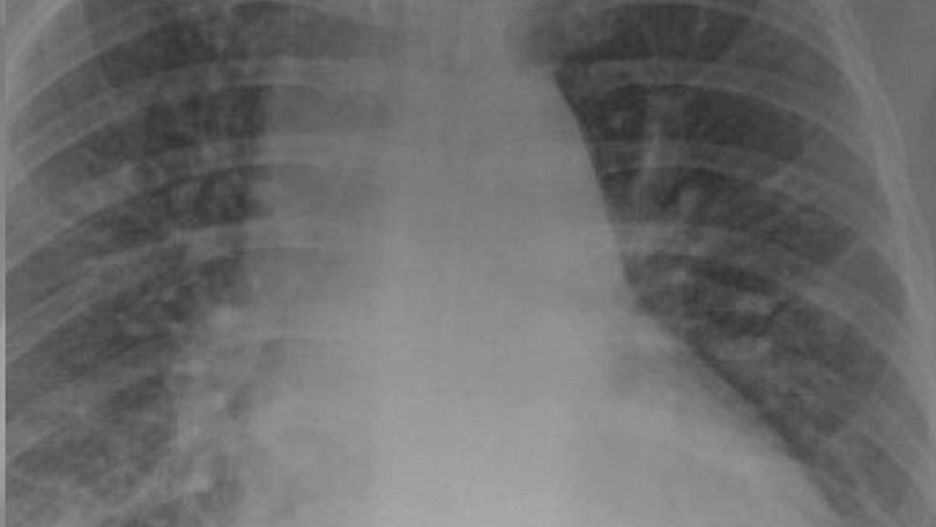

Na zdjęciu rentgenowskim chorego, ale zaszczepionego pacjenta nie widać żadnych niepokojących zmian w płucach. Natomiast u zakażonej, ale niezaszczepionej osoby płuca są zabielone. Lekarz wyjaśnia, że to zmętnienie płuc, czyli zacienienia typu mlecznego szkła widoczne dopiero na skanach tomografu komputerowego.

Zmętnienia płuc wskazują zwykle, że płuca są wypełnione np. płynem. To może nie tylko utrudniać oddychanie, ale także prowadzić do poważniejszych schorzeń.

płuca

Płuca osoby zaszczepionej i niezaszczepionej.